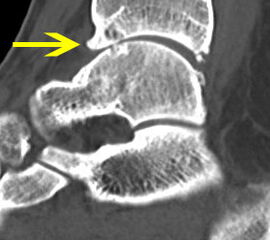

Abbildung 10, Video 5

Ventrales knöchernes Impingement durch einen großen Osteophyten an der Tibiavorderkante (Pfeil). Der Osteophyt wird mit einer Kugelfräse (3,5mm Durchmesser) reseziert. Für die Resektion und die abschließende Inspektion sollte in jedem Fall ein Portalwechsel erfolgen, um die vollständige Abtragung sicherzustellen. Gerade bei ausgedehnten osteophytären Anbauten kann es schwierig sein, intraoperativ abzuschätzen, ob ausreichend Knochen reseziert wurde. Hier bietet sich die intraoperative Kontrolle eines Bildverstärkers an. Bilder im seitlichen Strahlengang mit ggf. Innen- und Außenrotation des Sprunggelenks helfen, noch verbliebene Kanten medial und lateral am Sprunggelenk zu lokalisieren.